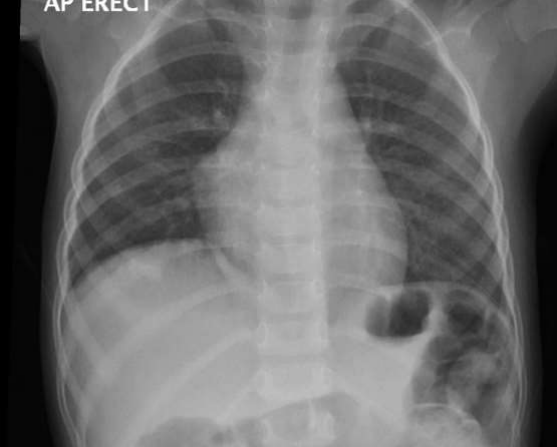

Clinically the patient was entirely normal and CXR done for her showed a marked elevation of the right diaphragm mostly diaphragmatic eventration (Figure 1) with a further request from the radiologist to rule out the presence of diaphragmatic hernia (Figure 2).

Figure 1: The initial chest x-ray of the patient showing a right sided diaphragmatic eventration